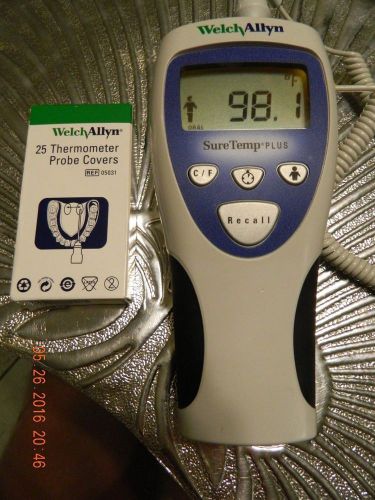

WELCH ALLYN SURE TEMP PLUS MEDICAL ORAL THERMOMETER #692 + 2 boxes PROBE COVERS

Welch Allyn SureTemp Plus 690 & 692 Thermometers w/ 1 Probe Lot of 6 *Parts*